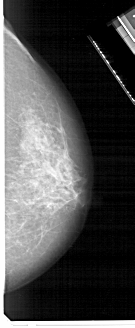

A_1706_1.RIGHT_CC

RIGHT_CC LINES 4906 PIXELS_PER_LINE 2011 BITS_PER_PIXEL 12 RESOLUTION 43.5 NON_OVERLAY